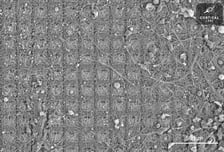

AI 칩에 인간 뇌 세포 붙였더니 전력 효율 '쑥"[월드콘]

영화 매트릭스는 기계가 인간을 시험관에 가두고 전기를 생산하는 부품으로 사용한다는 세계관 속에서 전개된다. 이 내용을 '인간'을 '뉴런'으로, '전기'를 '데이터'로 바꿔 현실화한 기업이 있다. 2019년 홍 웬 총 CEO(최고경영자)가 설립한 호주 기반 바이오테크 스타트업 '코티컬랩스'가 주인공이다. 코티컬랩스는 인간 뉴런(뇌 신경 세포)으로 구동하는 바이오 컴퓨터 개발을 목표로 한다. 지난달에는 뉴런 20만 개를 칩 위에 배양한 컴퓨팅 시스템 CL-1을 시켜 1인칭 슈팅 게임 '둠'을 플레이하게 하는 데 성공했다. CL-1은 크게 뉴런, 뉴런과 전기 신호를 주고받을 수 있는 칩 두 가지 요소로 구성된다. 칩은 뉴런이 어떤 신호를 내놓느냐에 따라 보상 또는 처벌하는 방식으로 뉴런을 학습시킨다. 뉴런이 올바른 반응을 내놓으면 규칙적인 전기 신호로 보상하고, 틀린 반응을 내놓으면 불규칙적인 신호를 보낸다. 신경 세포는 규칙적이고 예측 가능한 자극을 선호한다는 칼 프리스턴 런던대학 교수의 '자유 에너지 이론'에 근거한 방식이다.